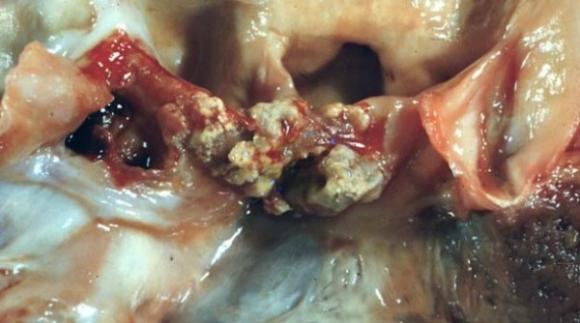

La nueva técnica consiste en un método de diagnóstico rápido para la endocarditis infecciosa, que es una afección generada por la infección de la membrana que recubre el interior de las cavidades del corazón. Sin un tratamiento adecuado puede generar otras complicaciones como embolia, arritmia e insuficiencia cardíaca.

Hay ocasiones que la identificación y aislamiento de los microorganismos causantes de endocarditis infecciosa suele ser dificultosa. La endocarditis con hemocultivos negativos constituye un serio problema. Lo novedoso del método es poder identificar los microorganismos causantes de endocarditis infecciosa en aquellas que cursan con hemocultivos negativos, cuyas causas más frecuentes son la administración de antimicrobianos previo al diagnóstico o una endocarditis infecciosa ocasionada por microorganismos con capacidad nula o limitada de crecimiento, que requieren de medios especiales para su desarrollo.